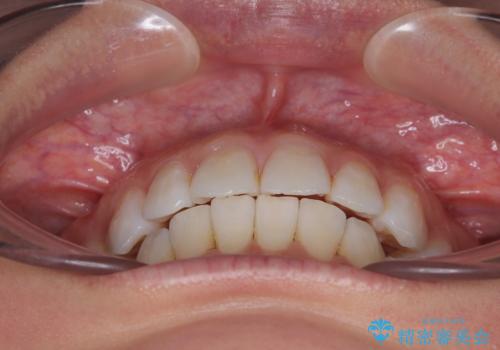

- 上下前歯の後戻りを気にして来院された患者様です。

インビザラインでの治療を希望されていて、デコボコの程度が中等度であり、安価なパッケージにて対応可能と判断されたため、インビザライン・モデレートを用いて矯正治療を行うこととしました。